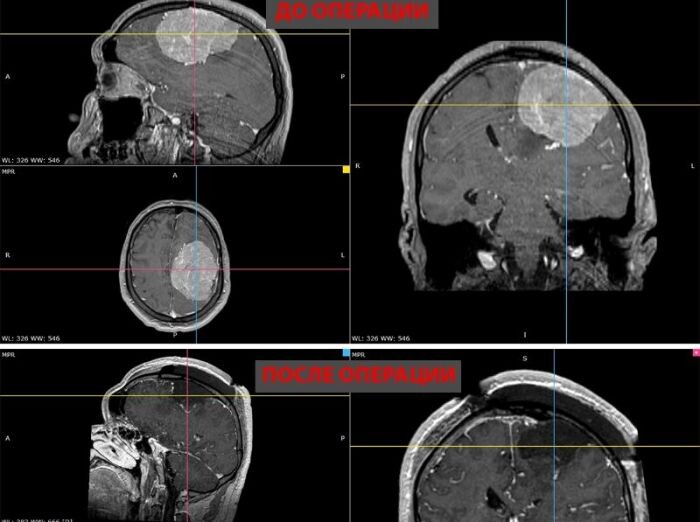

Гигантскую опухоль удалили молодому мужчине в центре Мешалкина

Гигантскую опухоль удалили молодому мужчине в центре Мешалкина Хирурги новосибирского центра Мешалкина удалили 35-летнему мужчине из Тюмени гигантскую опухоль головного мозга пациенту с опасной сопутствующей патологией – тромбоэмболией легочной артерии и тромбозом вен нижних конечностей. https://academ.info/news/society/49827/